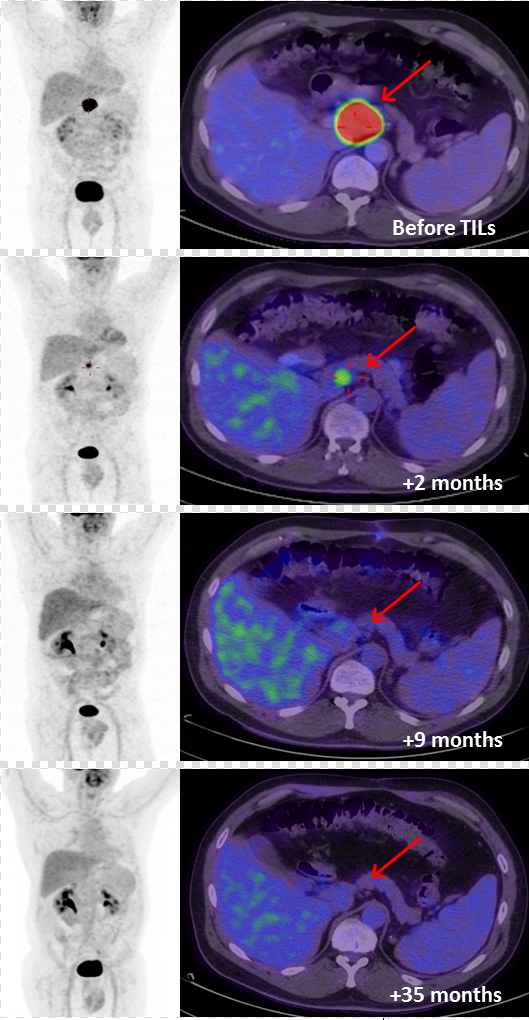

另有3例患者(M17、M24、M36)在TIL治疗前病灶无法切除,经治疗获得部分缓解(PR)后,接受了残留病灶手术切除,其中M17和M24在治疗后分别随访44个月和34个月,均持续缓解且无疾病迹象,这提示TIL-ACT初始缓解后,手术切除残留肿瘤病灶可能对患者有益。下图展示了患者M17治疗前后的FDG-PET/CT扫描结果。

▲图源“AACR”,版权归原作者所有,如无意中侵犯了知识产权,请联系我们删除